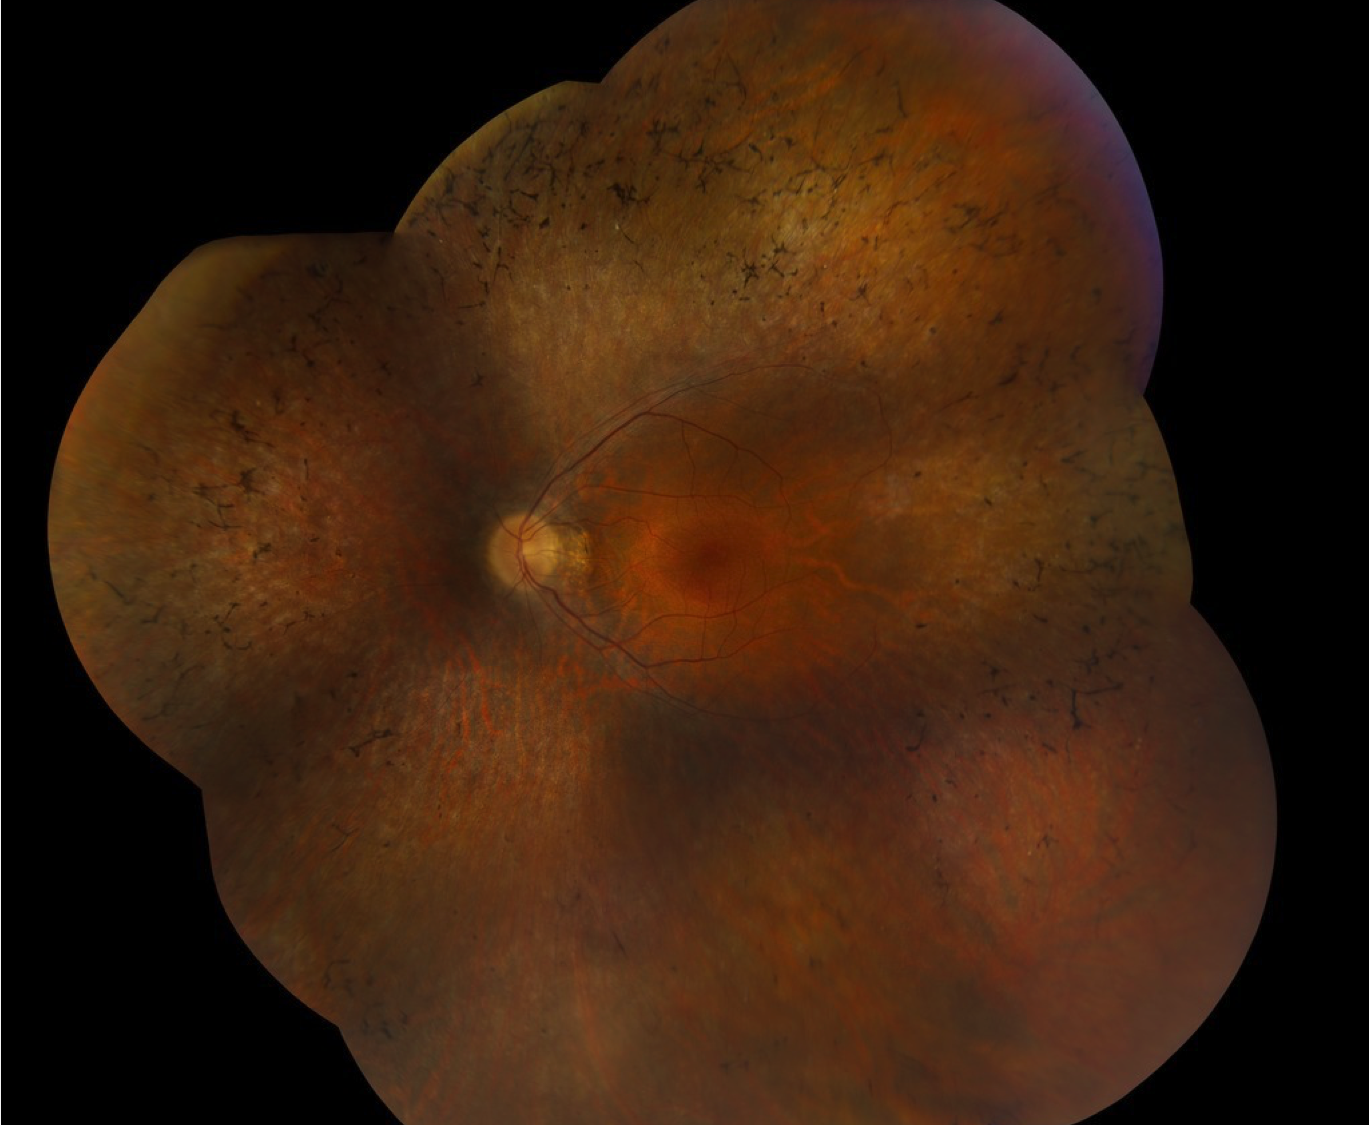

Case 12 is a 49 year old woman with 20/20 acuity. Her sister is similarly affected but her parents have normal acuity.

Color fundus photograph of the left eye.

In addition to her eye findings, the patient’s speech is abnormal and she has worn hearing aids in both ears since her hearing loss was first detected in early childhood.